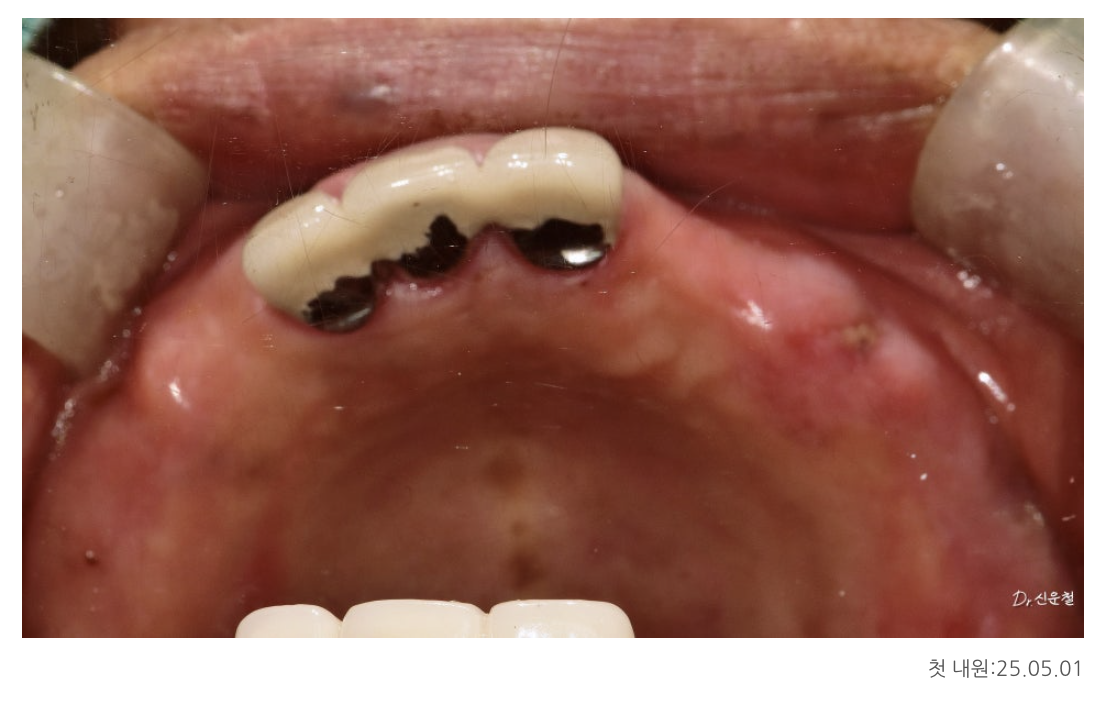

✔ 첫 내원 시 상태 (25.05.01)

앞니 세 개만 남아있는 상태

양쪽 어금니는 모두 상실

오래된 틀니 사용으로 잇몸뼈가 많이 닳아 있음

특히 위턱 뼈는 아래턱보다 부드럽고 힘을 받는 면적도 좁기 때문에

빠진 치아를 여러 개 한 줄로 길게 만들면

힘이 한쪽으로 쏠려 오래 버티기 어렵습니다.